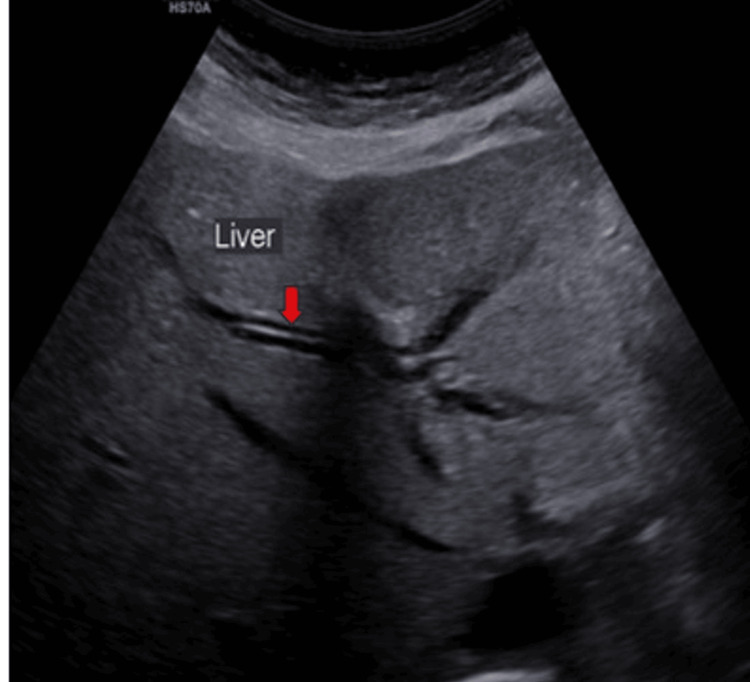

Ultrasound (US) examination revealed bilobar intrahepatic biliary radicle (IHBR) dilatation (Figure 1), and the gallbladder appeared overdistended with large, heterogeneously hypoechoic content devoid of vascularity on color Doppler (Figure 2). The gallbladder wall appeared thickened, measuringapproximately 4 mm. Furthermore, the proximal CBD appeared mildly dilated, measuring 8 mm, with a heterogeneously hypoechoic lesion within the midportion causing its narrowing (Figure 3). Multiple subcentimetric to enlarged necrotic lymph nodes were also observed in the porta-hepatis, periportal, and retroperitoneal regions (Figure 4).